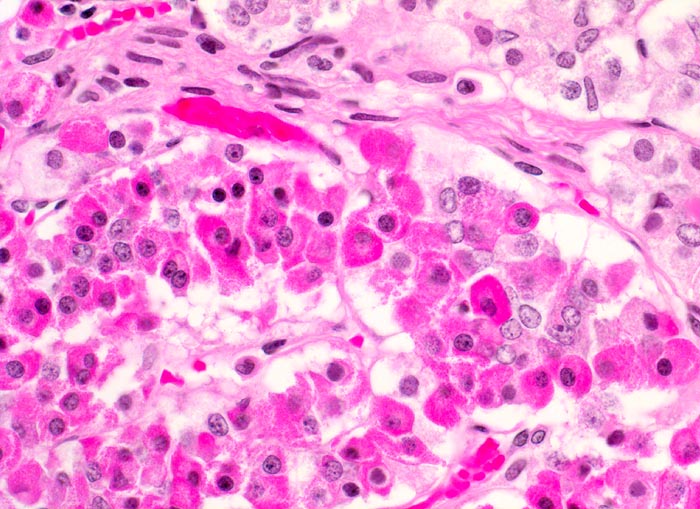

Adenohypophyse

Normalbefund

Hypophyse

Adenohypophyse mit verschiedenen Zelltypen. Die Zellen haben unterschiedlich gefärbtes Zytoplasma. In der HE Färbung können Azidophile, Basophile und Chromophobe Zellen nicht sicher voneinander abgegrenzt werden.

Histologie

400